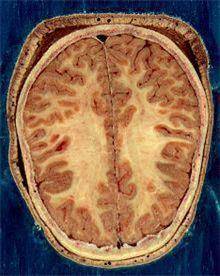

![뇌의 백질과 회색질 [출처: 위키백과]](https://img4.daumcdn.net/thumb/R658x0.q70/?fname=https://t1.daumcdn.net/news/202302/06/yonhap/20230206103659274rhpu.jpg)

뇌 백질 변성은 뇌경색 환자의 뇌 영상에서 가장 흔하게 접할 수 있는 이상 소견으로 뇌 용적이 줄어들고 특히 대뇌피질 위축이 동반된다.

뇌는 신경 세포체로 구성된 겉 부분인 대뇌 피질과 신경세포들을 서로 연결하는 신경 섬유망이 깔린 속 부분인 수질로 이루어져 있다. 피질은 회색을 띠고 있어 회색질(gray matter), 수질은 하얀색을 띠고 있어 백질이라고 불린다.